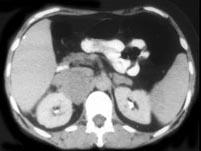

问题 男,65岁,全身浅表淋巴结肿大,请根据所示图像,选择最可能诊断 ( )

选项 A、左肾外伤出血 B、尿外渗 C、左肾转移瘤 D、淋巴瘤左肾周浸润 E、左侧肾癌

答案 D